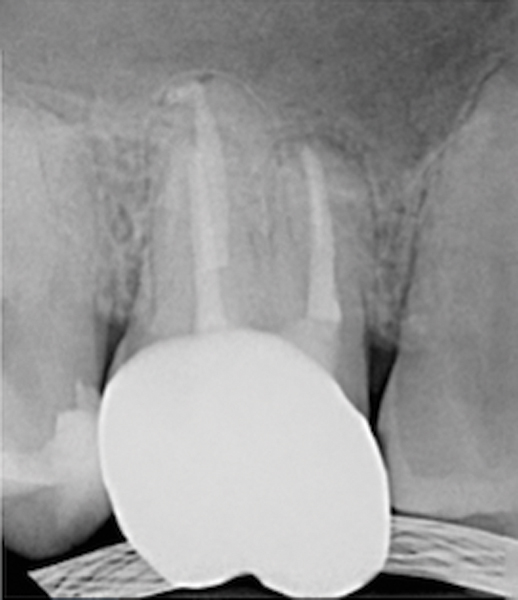

Fig 4. and Fig 5. Before and after radiographs of bioceramic sealer hydraulically moved with the gutta-percha point. Note that the cold hydraulic technique results in lateral canal “puffs” similar to the warm vertical technique. Courtesy of Dr. Gilberto Debelian.

Figure 4

Figure 5

Pre-mixed BC Sealer is the only pure medical-grade bioceramic product available as a sealer for endodontic obturation. It has the same basic chemical composition as the other pre-mixed bioceramic products, but it is less viscous, which makes its consistency ideal for sealing root canals. It is used with a gutta-percha point, which is impregnated on the surface with a nano particle layer of bioceramic. The gutta-percha is used primarily as the delivery device (plugger) (Figure 1 through Figure 3) to allow hydraulic movement of the sealer into the irregularities of the root canal and accessory canals (Figure 4 and Figure 5).